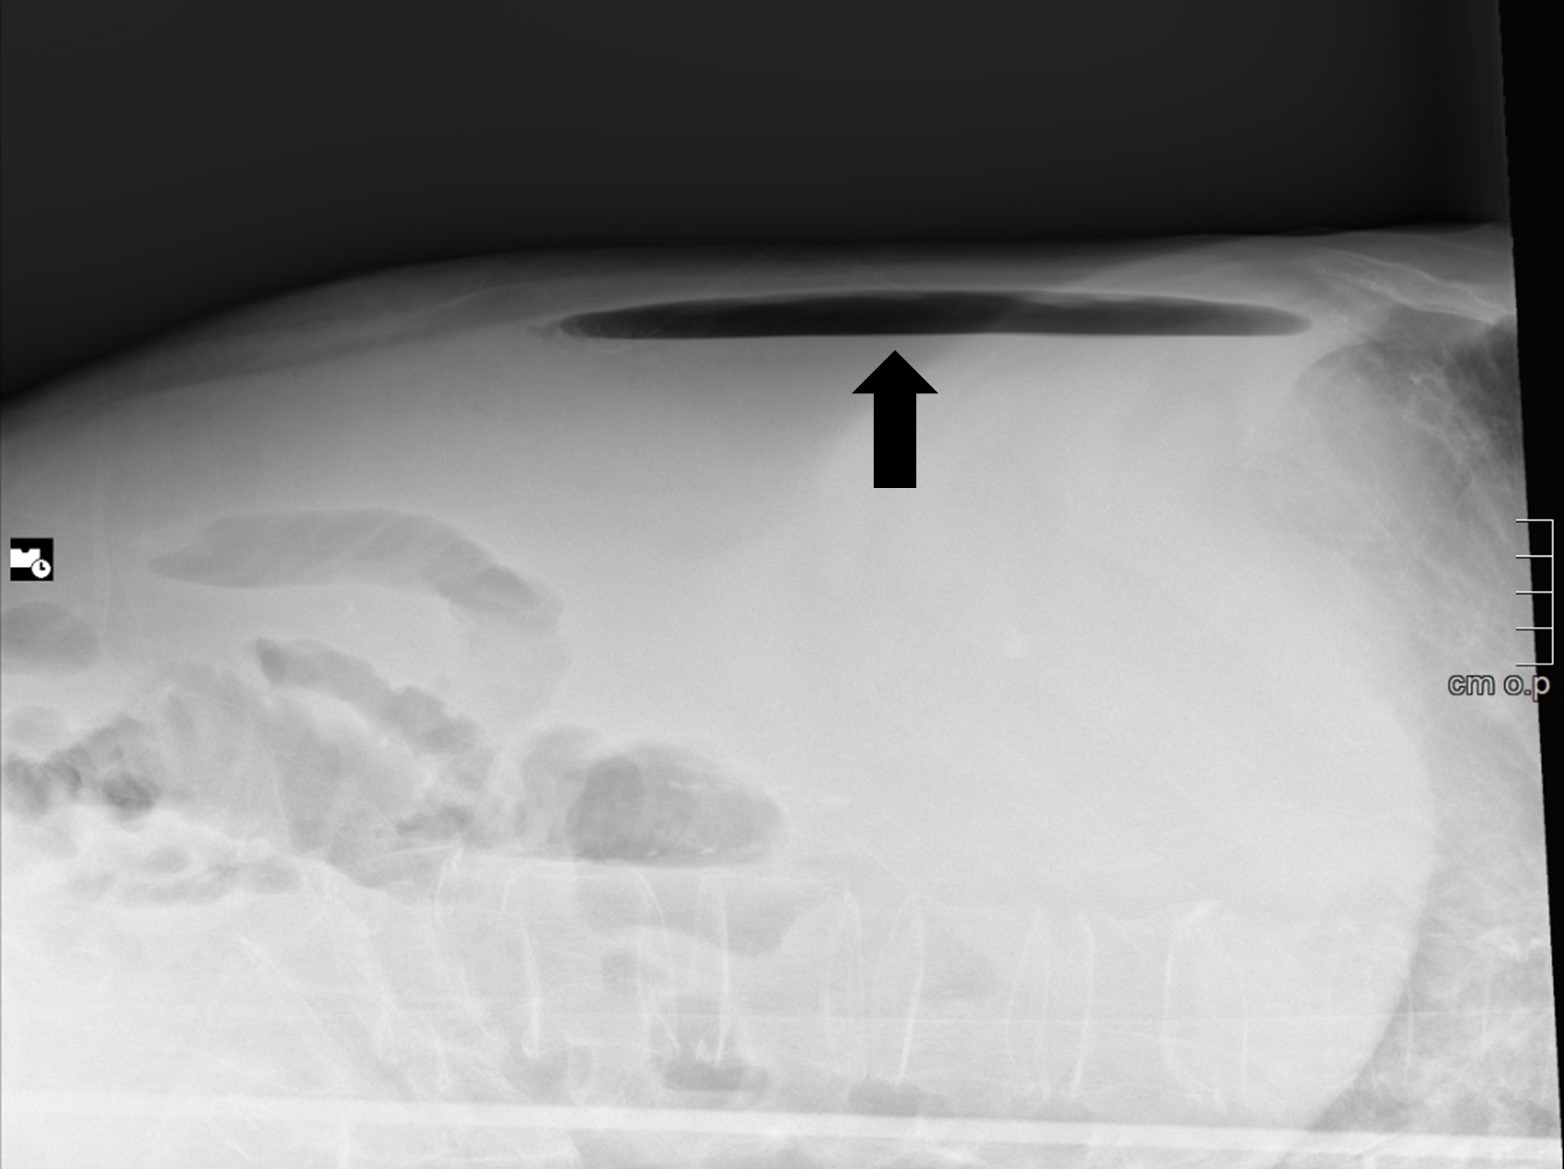

A tangential abdominal radiography was obtained, in this context, and a gas level on the non-dependent portion of the abdomen was identified (Figure 1). This finding raised the suspicion of pneumoperitoneum and, therefore, a CT was performed. On CT, a markedly distended stomach, as well as a distended oesophagus and free abdominal fluid were identified, implying an obstructive event (Figure 2). The inferior portion of the stomach and some intestinal loops were contained on the right inguinoscrotal hernia, making this the most probable cause for the obstruction (Figure 3).

Figure 1: Tangential abdominal radiograph showing an air-fluid level, that corresponded to gastric bubble (black arrow).